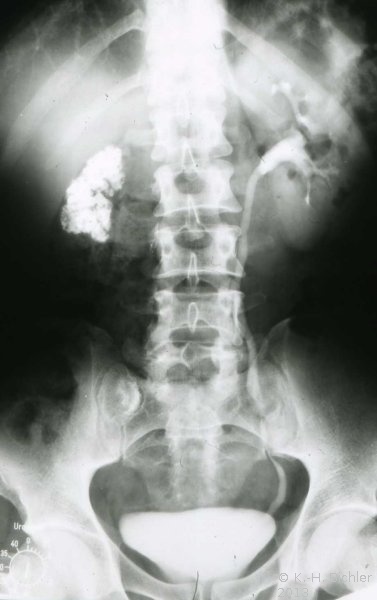

Anfänglich treten nur wenig typische allgemeinentzündliche Symptome auf. Später bestehen entsprechend den entzündlichen Veränderungen in den verschiedenen Organen (Nieren, Harnblase, Prostata, Nebenhoden, Harnröhre) z.B. Brennen beim Wasserlassen (Dysurie) Schmerzen in der Dammgegend, Hoden- und Nebenhodenschwellung, Bakteriurie, Hämaturie und Hämospermie auf.

Häufigste Symptome sind Hämaturie bzw. Dysurie und Schwellung von Hoden und Nebenhoden (z.T. schmerzlos).